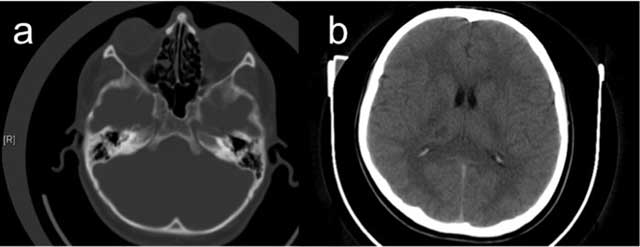

A 27-year-old male patient with an unremarkable medical history presented with acute onset of severe headache, dizziness and disequilibrium, and left sided weakness. Unenhanced CT revealed a hypodense lesion in the right thalamic and subthalamic region about 1 cm in diameter and an absent right ICA and bony carotid canal (Figure 2). On MRI, a well defined T2-hyperintense, T1-hypointense, contrast-enhancing lesion was seen in the right thalamus and subthalamic region consistent with sub-acute infarction (Figure 3). Cranial and cervical MR angiography showed right ICA agenesis and anomalous origin of the ophthalmic artery derived from right MCA. The aortic arch and major aortic branches were normal.

Figure 2

An axial CT image at bone window reveals absent right bony carotid canal (a); cranial CT image reveals hypodense lesion at right subthalamic region about 1 cm in diameter (b) in Case 2.